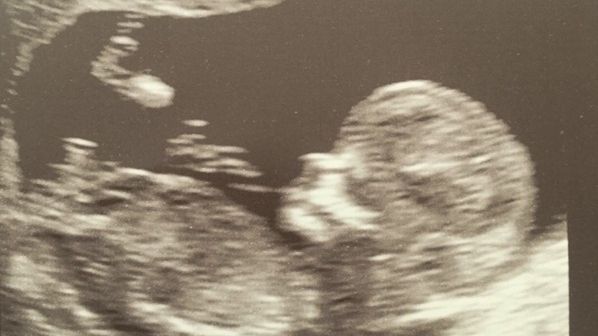

24 aug. 2016, 23:47ActualUn celebru cântăreţ american, tată pentru a 15-a oară! Vezi cine este tatăl erou - FOTO

26 mai 2016, 19:30MondenVeste surprinzătoare de la un cunoscut cântăreţ: "Voi fi tată din nou! Sunt atât de fericit!"